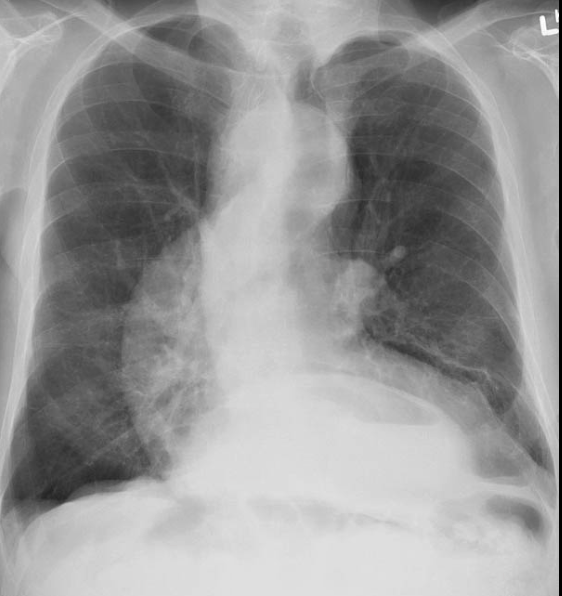

RA of HH CXR

large HH can show on CXR as a mass behind the mediastinum